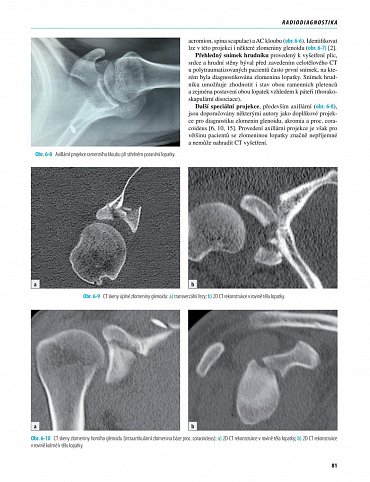

První monografie věnovaná zlomeninám lopatky v domácí i světové literatuře. Kniha vysvětluje obecné principy diagnostiky a terapie zlomenin lopatky doprovázené podrobným rozborem 519 zlomenin lopatky u dospělých, z toho 150 operovaných případů, 39 zlomenin u dětí a dospívajících.